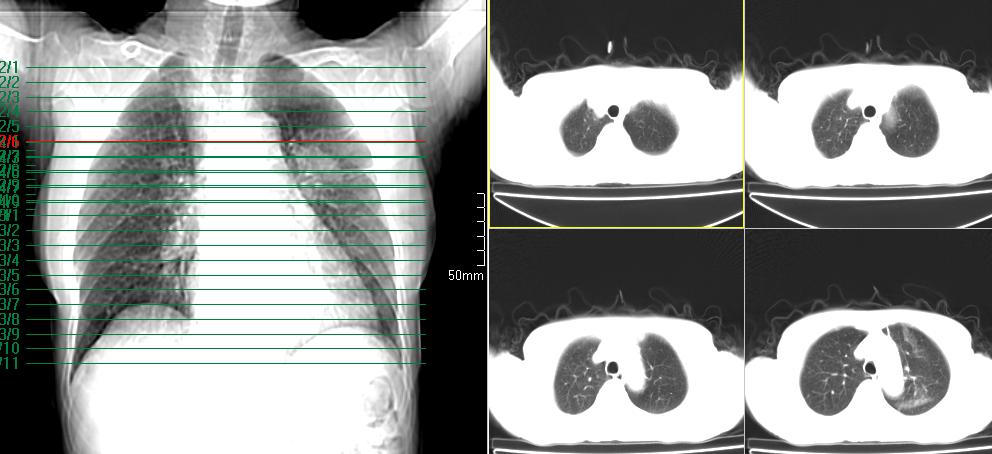

标题: CT26857:女,60岁,胃部不适前来就诊,不咳嗽,乏力,胸椎 [打印本页]

标题: CT26857:女,60岁,胃部不适前来就诊,不咳嗽,乏力,胸椎

1、胸椎有骨质破坏伴周软组织,考虑胸椎转移。2、考虑左肺上叶尖后段支气管开口区周围型肺癌可能。

1、胸椎有骨质破坏伴周软组织,考虑胸椎转移。2、考虑左肺上叶尖后段支气管开口区周围型肺癌可能。建议行纤支镜检查!

1、胸椎有骨质破坏伴周软组织,考虑胸椎转移。2、考虑左肺中央型肺癌可能。

椎体有高密度影,多系转移。

支持中央型肺癌,胸椎转移。

1)考虑左肺中央型肺癌。2)胸椎转移瘤不排除;建议行mri检查。